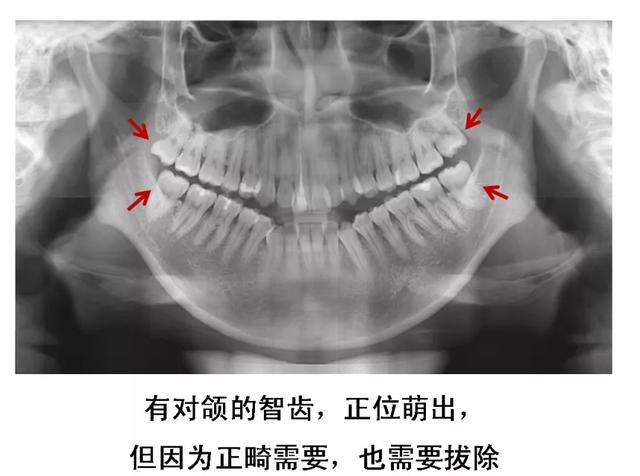

5、没有对颌牙的智齿

这种智齿不能与对颌牙齿建立正常咬合关系,长时间可导致颞下颌关节弹响、张口疼痛、夜磨牙等。没有对颌牙的智齿还会伸长,智齿和邻牙间容易食物嵌塞,并导致邻接面龋。

6、牙齿需要矫正,以及在12-16岁做过矫正的小朋友,需要根据正畸医生的建议,及时拔除智齿,以获得完美的牙列和脸型!